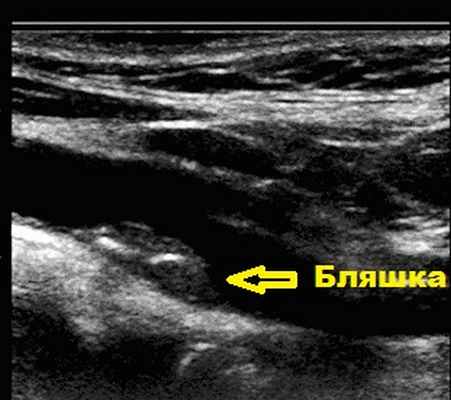

На УЗИ сосудов шеи и головы атеросклеротическая бляшка выглядит следующим образом:

![]()